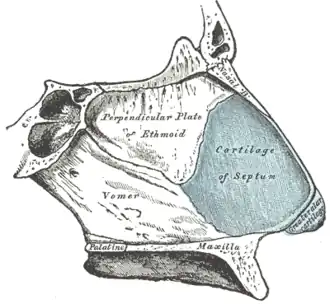

Sagittalschnitt, mit Blick nach innen (medial) auf das Nasenseptum

Sagittalschnitt, mit Blick nach innen (medial) auf das Nasenseptum -

Starke Verbiegungen der Nasenscheidewand (Septumdeviationen) behindern die Nasenatmung. Am vorderen Rand der knorpeligen Nasenscheidewand liegt der Septumschwellkörper mit dem Locus Kiesselbachii (Kiesselbachscher Wulst), der Prädilektionsstelle für das Nasenbluten.[20]